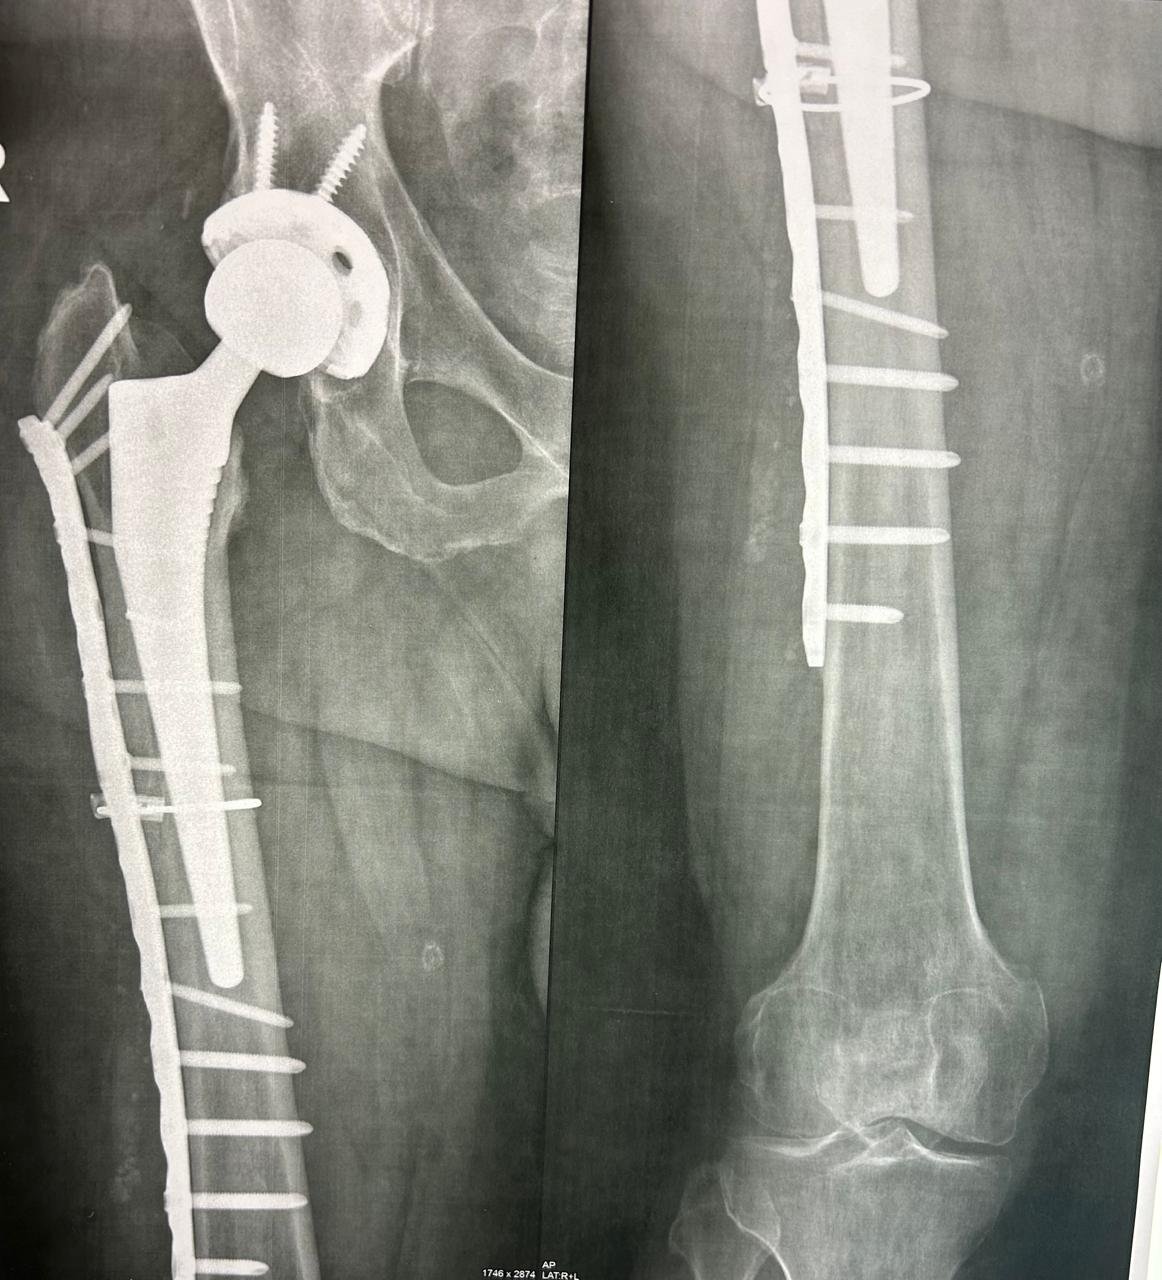

يُعد د. عمرو عبد القادر حماد واحدًا من أبرز خبراء جراحة العظام في مصر، بخبرة تمتد منذ عام 2000 وحتى الآن. يتميز بخبرة واسعة في جراحات المفاصل الصناعية، ومناظير الركبة والكتف، وعلاج إصابات الرياضيين، مع سجل حافل من النجاحات في استعادة الحركة والحياة الطبيعية لآلاف المرضى.